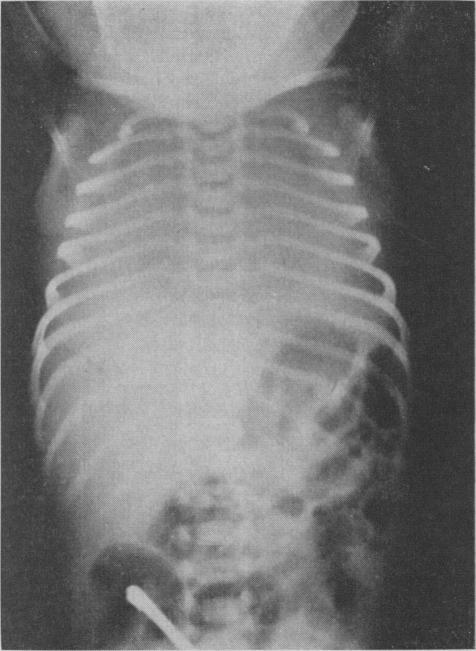

Four hundred and thirty infants selectively referred to the Newborn Unit of The Hospital for Sick Children, Toronto, with the symptom of respiratory distress, were reviewed. There were 142 cases of the "idiopathic respiratory distress syndrome" (IRDS), of which 67 were fatal. The remainder included 100 cardiac (76 deaths), 63 extra-pulmonary (28 deaths) and 109 other specific pulmonary conditions (54 deaths). Of the 109, half were due to massive aspiration. Serial observations and radiographs led to correct clinical diagnosis in 85% of necropsy-proved cases of IRDS and in a comparable proportion of all other conditions. The incidence and mortality rate of IRDS were twice as high in males as in females. A significant number of premature infants have transient respiratory distress after birth, and diagnostic criteria for inclusion in any study should be defined in detail. This study emphasized the large contribution of disorders of the respiratory and cardiac systems to neonatal mortality and led to the formation of a special department for intensive care and research in these conditions.

对430名因呼吸窘迫症状而被选择性转诊至多伦多病童医院新生儿科的婴儿进行了回顾性研究。其中有142例“特发性呼吸窘迫综合征”(IRDS),其中67例死亡。其余包括100例心脏疾病(76例死亡)、63例肺外疾病(28例死亡)和109例其他特定肺部疾病(54例死亡)。在这109例中,一半是由于大量吸入所致。系列观察和X光片检查使得85%经尸检证实的IRDS病例以及所有其他疾病中相当比例的病例得到了正确的临床诊断。IRDS的发病率和死亡率男性是女性的两倍。相当数量的早产儿出生后有短暂呼吸窘迫,任何研究中的纳入诊断标准都应详细界定。本研究强调了呼吸和心脏系统疾病对新生儿死亡率的巨大影响,并促使成立了一个针对这些病症的重症监护和研究特别科室。